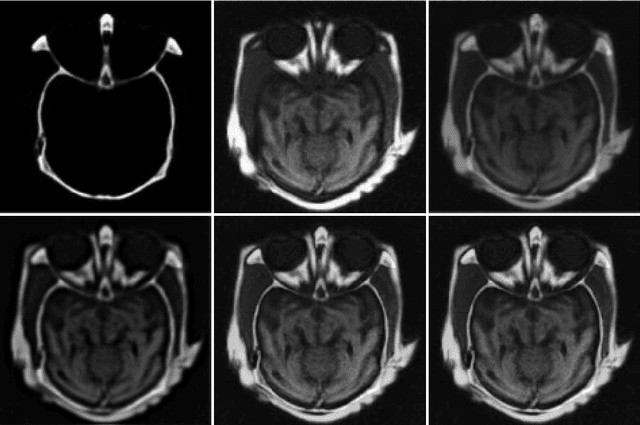

Abstract:The L1 norm regularized least squares method is often used for finding sparse approximate solutions and is widely used in 1-D signal restoration. Basis pursuit denoising (BPD) performs noise reduction in this way. However, the shortcoming of using L1 norm regularization is the underestimation of the true solution. Recently, a class of non-convex penalties have been proposed to improve this situation. This kind of penalty function is non-convex itself, but preserves the convexity property of the whole cost function. This approach has been confirmed to offer good performance in 1-D signal denoising. This paper demonstrates the aforementioned method to 2-D signals (images) and applies it to multisensor image fusion. The problem is posed as an inverse one and a corresponding cost function is judiciously designed to include two data attachment terms. The whole cost function is proved to be convex upon suitably choosing the non-convex penalty, so that the cost function minimization can be tackled by convex optimization approaches, which comprise simple computations. The performance of the proposed method is benchmarked against a number of state-of-the-art image fusion techniques and superior performance is demonstrated both visually and in terms of various assessment measures.